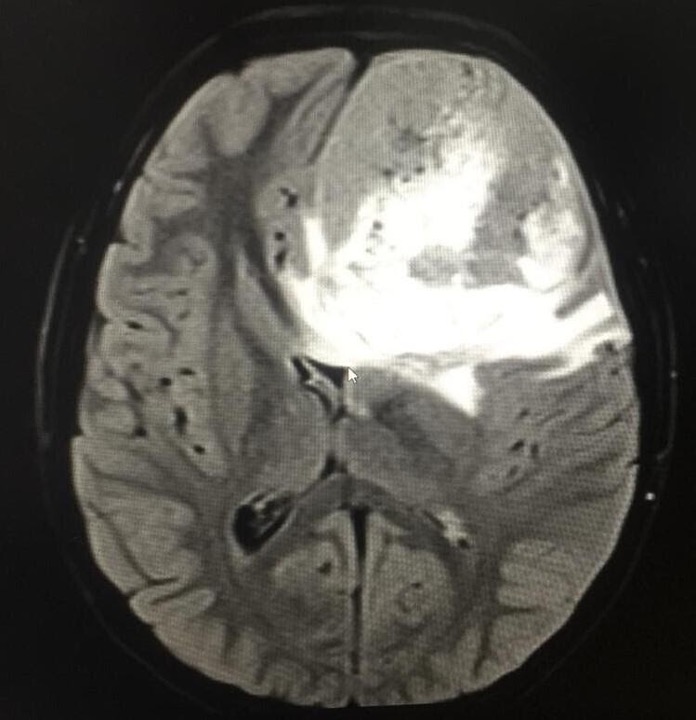

Al examen neurológico se evidencia que la paciente presenta dolor de 6/10 por escala análoga del dolor y papiledema derecho, sin focalización, resto del examen físico normal. Por lo anterior se consideró paciente con cefalea con banderas rojas por lo que se solicitó resonancia magnética cerebral simple. Se evidenció lesión expansiva intra-axial de aspecto heterogéneo en todas las secuencias con predominio de hipointensidad en T1 e hiperintensidad en T2 que se rodea de escaso edema perilesional con escaso componente hemorrágico hacia posterior con restricción de la difusión, con diámetros de 66.44mm anteroposterior x 52.11 mm de alto x 58 mm de ancho.

Adicionalmente, presentaba importante efecto compresivo que desvía a las estructuras de la línea media de izquierda a derecha por debajo de la hoz y deforma el sistema ventricular, con hernia del hipocampo izquierdo (Ver figura 1). Ante estos hallazgos el servicio de neurología solicitó una resonancia magnética contrastada e inició tratamiento con analgesia y corticoides para prevención de hipertensión endocraneana. Ante los hallazgos descritos, se realizó una junta con los servicios de neuroradiología, neurocirugía y hematooncología pediátrica quienes consideraron que se trataba de tumor glial (oligodendroglioma) en lóbulo frontal izquierdo que se asociaba a herniación cerebral subfalcina con desviación de línea media de 1.6mm, con edema cerebral vasogénico e importante efecto de masa que se acompañaba de síntomas de hipertensión endocraneana (cefalea, emesis y papiledema).

Figura 1. Resonancia magnética cerebral

A. Corte Axial B. Corte coronal. Lesión expansiva intra-axial de aspecto heterogéneo con predominio de hipointensidad en T1 e hiperintensidad en T2 que se rodea de escaso edema perilesional con escaso componente hemorrágico hacia posterior con restricción de la difusión. Diámetros de 66.44mm AP x 52.11 mm de alto x 58 mm de ancho. Importante efecto compresivo que desvía las estructuras de la línea media de izquierda a derecha por debajo de la hoz y deforma el sistema ventricular, con hernia del hipocampo izquierdo